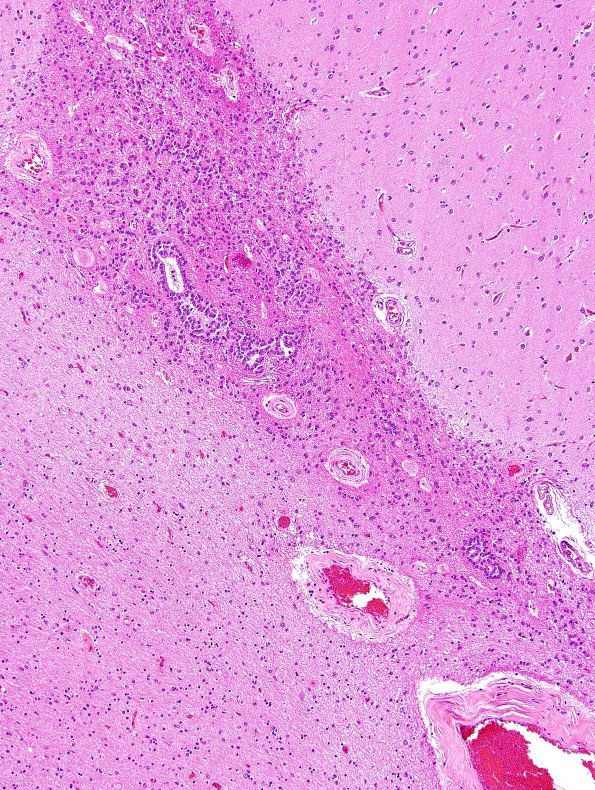

Ependymal Fusion Seam

Higher magnification of image #10A1. (H&E)